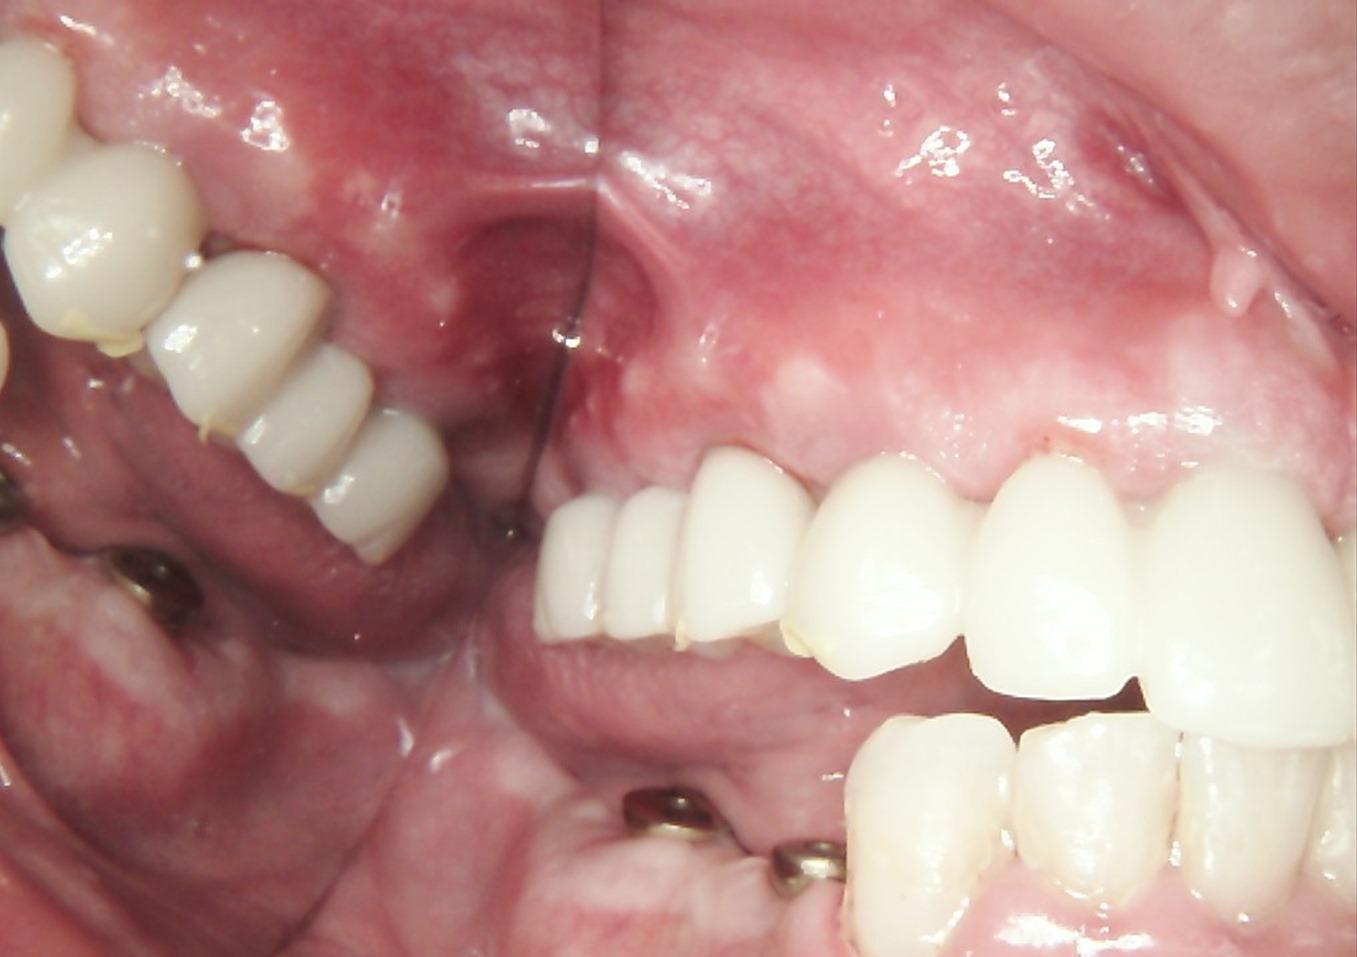

Currently, the patient is wearing the provisional PMMA prosthesis. He is attending regular professional hygiene appointments and adhering to a strict home care regimen. This transitional period allows for the evaluation of the function and esthetics of the PMMA prosthesis, so that any necessary adjustments can be made before fabricating the final restoration, ensuring an optimal outcome.

The patient’s appearance at this stage demonstrates a natural and harmonious result.